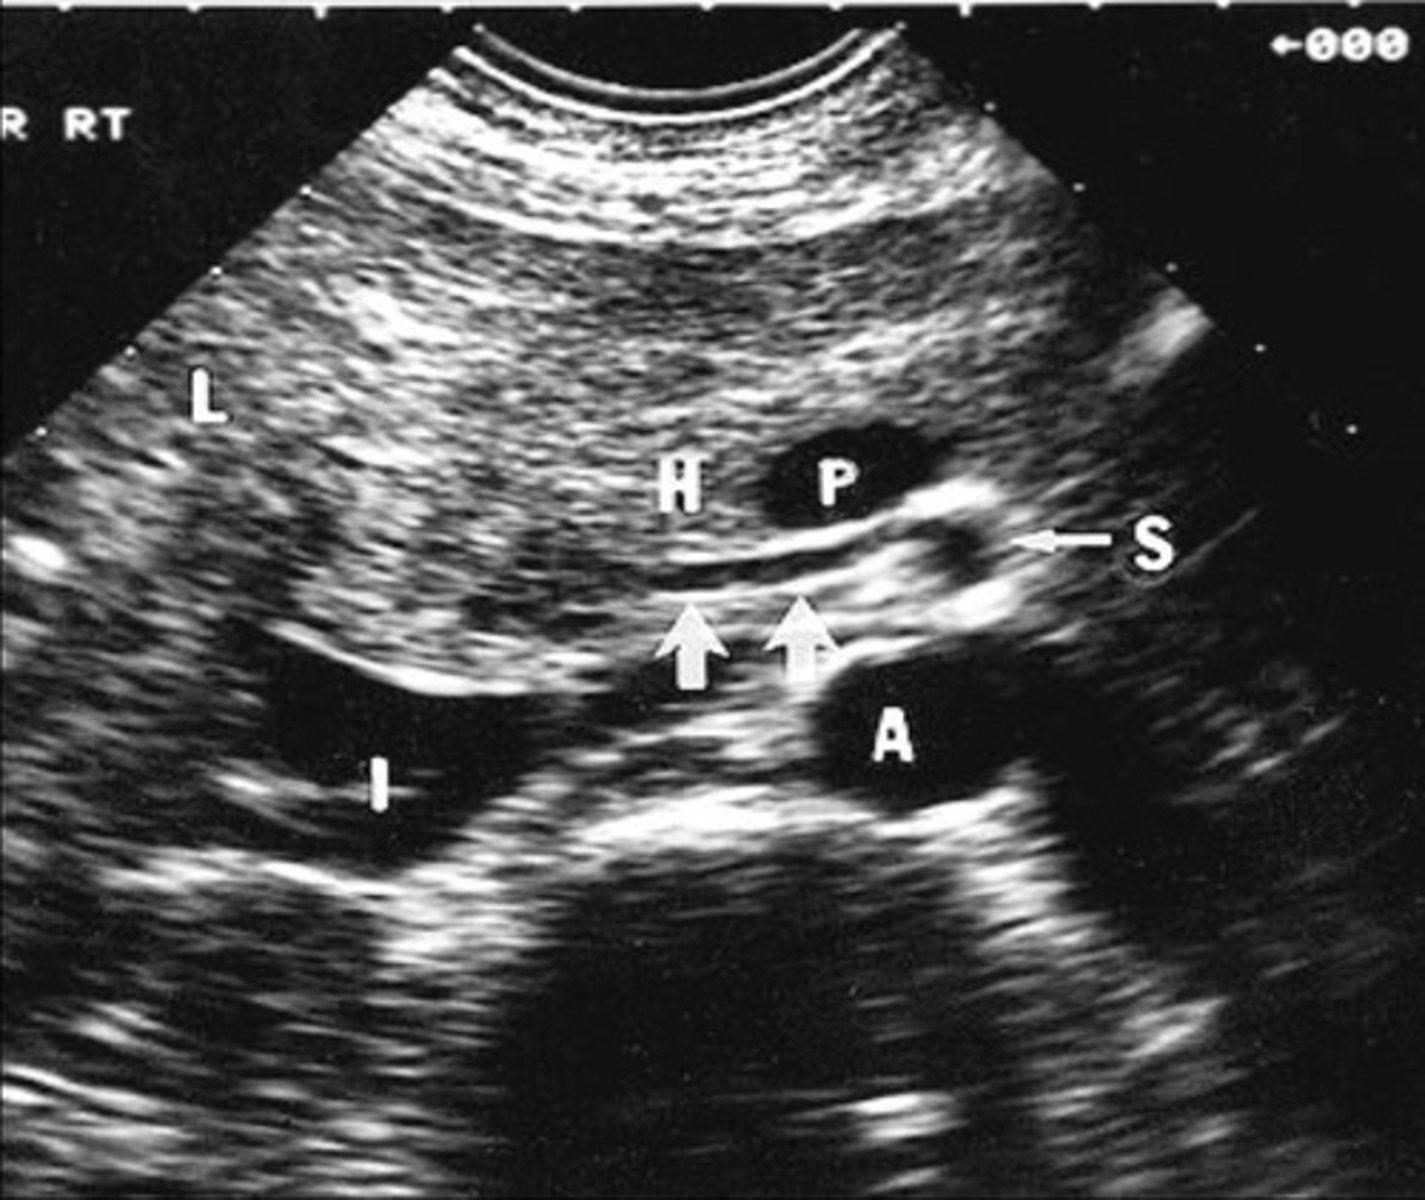

Celiac Artery Occlusion

Results in SMA collaterals diverting blood through gastroduodenal artery toward the liver and spleen

Pre-Hepatic/Inflow Vessels

Portal Vein

Hepatic Artery